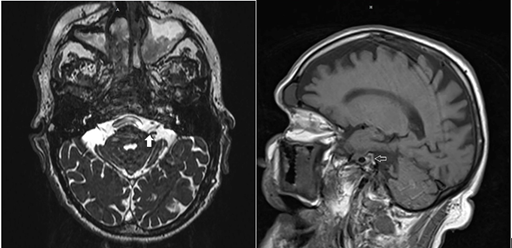

Bell’s palsy is a frequent neurological condition accounting for 72% of facial weakness.2,9 It consists of an acute lower motor neuron facial paralysis, which is often preceded by a history of severe aching pain in and around the ear during the 24 hours prior to onset.10 Different than Bell’s palsy of viral or inflammatory origin, there are no pain symptoms with LMN CN VII facial palsy due to stroke. This is a diagnostic clue for physicians. With Bell’s palsy, there is an identifiable swollen or entrapped CN VII at the level of the internal acoustic meatus identifiable on CT-scan or MRI (Figure 3).10,11 On the other hand, in the case of perforating prepontine long circumferential artery occlusion, the CN VII structure is normal. Under these circumstances, a CT-scan with and without contrast, as well as a CT-angiogram may be insufficient. We propose that DWI MRI may be used as a gold standard for investigation. However, as reported by Oppenheima et al.,12 a false-negative DWI study is not uncommon during the first 24 hours of ischemic stroke, This is especially true for the vertebrobasilar territory distribution strokes.

Figure 3 A & B. MRI demonstrates a structurally normal CN VII (Arrow heads) entering the internal acoustic meatus with no evidence of swollen and/or entrapped nerve.